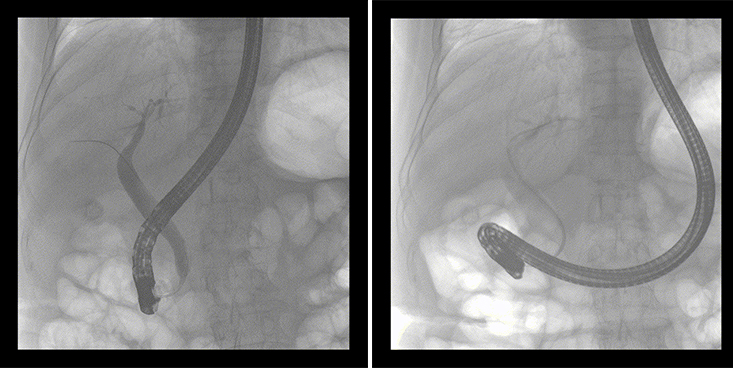

一位86歲的女性患者近來出現(xiàn)腹痛,入院后CT檢查并結(jié)合臨床表現(xiàn)被診斷為急性膽囊炎伴膽囊結(jié)石。經(jīng)專家團(tuán)隊協(xié)商并與患者家屬溝通,決定對患者實施經(jīng)內(nèi)窺鏡逆行胰膽管造影(ERCP)。

ERCP(經(jīng)十二指腸鏡下逆行胰膽管造影)現(xiàn)已成為比較成熟的微創(chuàng)介入技術(shù),被廣泛的應(yīng)用于臨床,ERCP也是消化內(nèi)鏡領(lǐng)域難度大、風(fēng)險大、技術(shù)復(fù)雜的微創(chuàng)手術(shù),其并發(fā)癥多為致命性,ERCP手術(shù)對醫(yī)生的要求很高,因此,ERCP醫(yī)生又被稱為“刀尖上的舞者”。因為手術(shù)難度較大,過程復(fù)雜,需要C形臂精準(zhǔn)的配合,對影像清晰度的要求也非常高。

普愛醫(yī)療移動式平板中C為本次ERCP手術(shù)提供實時無損高清影像,幫助醫(yī)生精準(zhǔn)定位。“成像效果非常棒!完全不輸國際大牌的醫(yī)學(xué)影像設(shè)備……”鼓樓醫(yī)院江北國際醫(yī)院內(nèi)鏡中心手術(shù)團(tuán)隊對普愛醫(yī)療移動式平板中C的成像效果給與了高度的評價。

在消化內(nèi)科主任的領(lǐng)導(dǎo)和多科室全力配合下,南京鼓樓醫(yī)院江北國際醫(yī)院成功完成了首例ERCP手術(shù)。